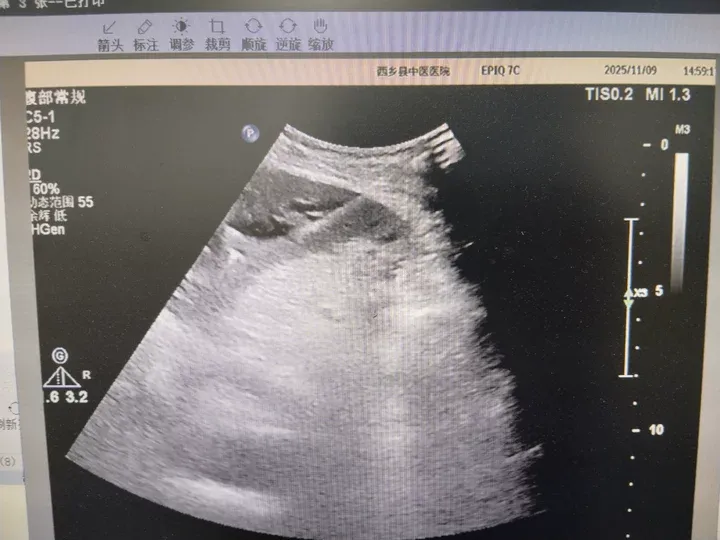

手术过程专业、严谨,科室团队密切配合,张伟主治医师凭借丰富的经验和沉稳的操作,在彩色多普勒超声的实时引导与监视下,精准规划穿刺路径,避开重要血管,将一根细长的引流管经皮肤、肝脏,成功置入目标肝内胆管。瞬间,淤积的墨绿色胆汁被顺利引流出体外。术后24小时内,引流胆汁量达1765ml,患者皮肤黄染等症状得到迅速、有效的缓解,转危为安。